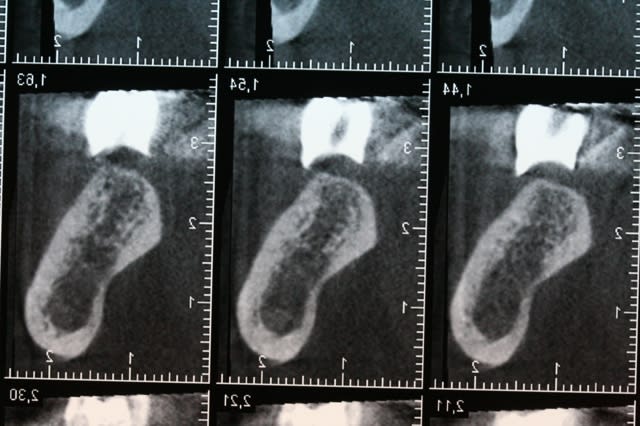

je préfère avoir une dent radio opaque car l'image obtenue sur la radio me montre mon couloir prothétique ainsi que mon axe.

avec simplement de la gutta , tu ne vois que l'axe implantaire, pas les limites de mise en place de ton implant.